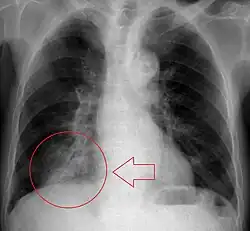

Imaging

Radiologic studies may be done to image the chest wall, lungs, and airway to evaluate and diagnose conditions that may be contributing to aspiration, and also to diagnose complications of previous aspiration.

Chest X-rays can be useful in the diagnosis of aspiration pneumonia but may be negative early in the course.[12] Chest CT Scan can identify the presence of a pneumonia as well, and can also assist in characterizing abscesses, foreign objects, or pleural disease.